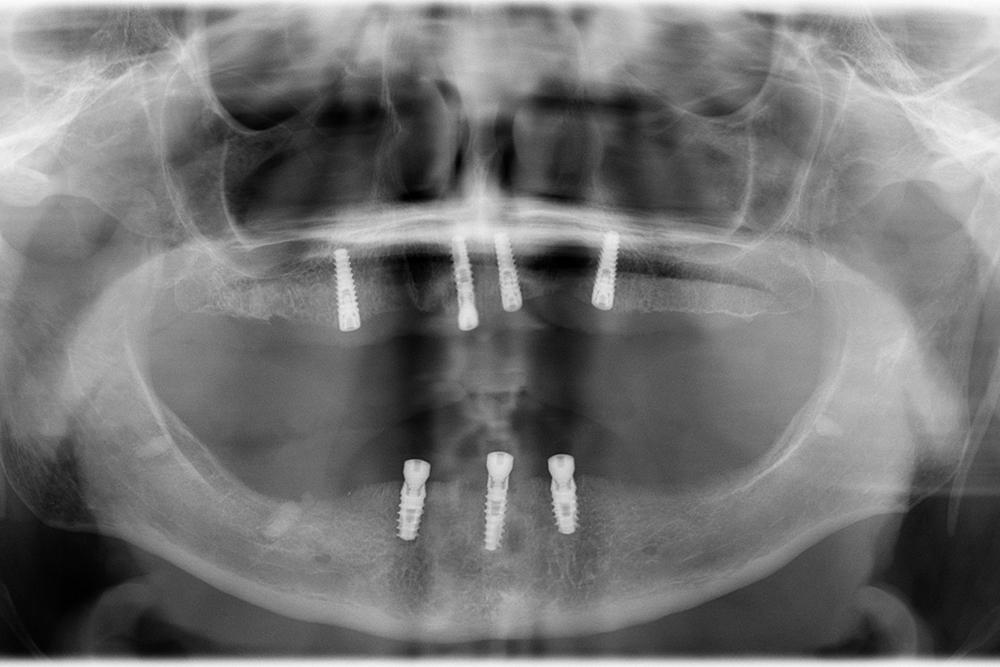

Ripristino dell’arcata superiore ed inferiore su overdenture su barra